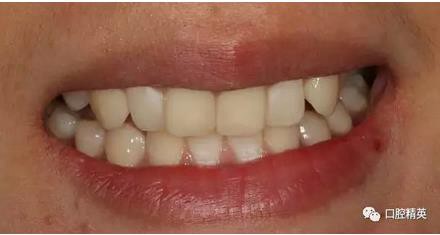

修復體戴入

口內(nèi)正側(cè)位及切端特寫

從側(cè)位照可看出遠中切角略有回收